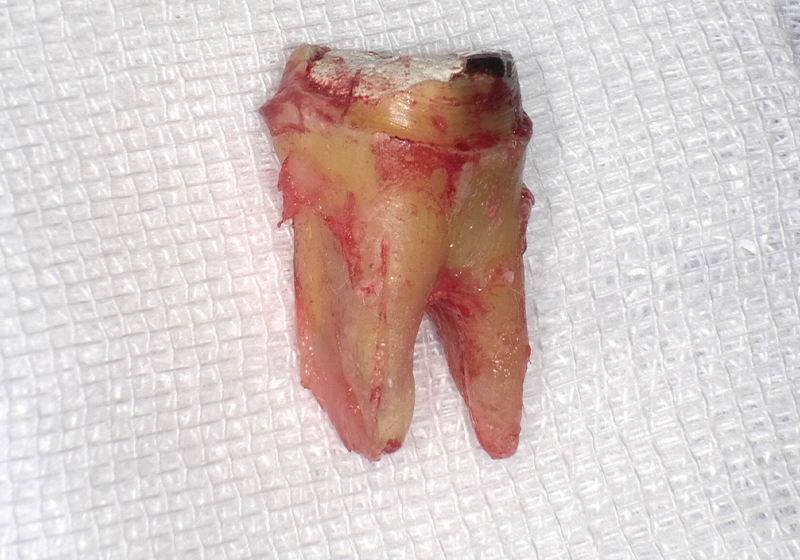

【③抜歯した歯の根には大きな亀裂があった】

親知らず

【④移植のために右下から抜歯した親知らず】